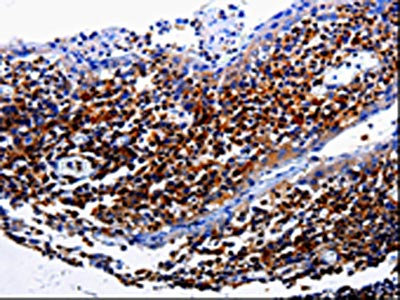

圖片:

應(yīng)用范圍:ELISA,IHC

Application Recommended Dilution ELISA 1:2000-1:5000 IHC 1:25-1:100 -